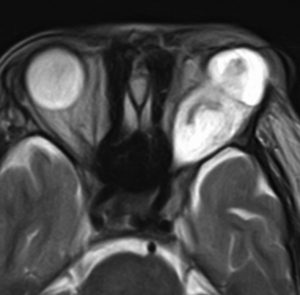

左が16歳,右が23歳の時のMRI画像です。太く見えた視神経が,大きな塊となりました。ガドリニウム増強で,腫瘍の内部が部分的に増強されます。眼球が突出して目を閉じることができず,むき出しになりました。8歳から23歳まで,15年間かかってゆっくり大きくなったし眼窩内神経膠腫です。

CTでは高度の眼球突出があり,腫瘍の辺縁が石灰化していて視神経鞘を含めて極めて硬い線維性腫瘍となっていることがわかります。T2強調画像では高信号で腫瘍が増大傾向を示し,一部が嚢胞性であることがわかります。下のT1増強像では腫瘍の中心部分に増強される増殖部位があることがわかります。

病理所見では,幼児型のpilomyxoid astrocytomaの部分が混在します。その部分が増殖と腫瘍増大に関わっています。T2強調画像で高信号でガドリニウム増強される部分です。

myxoidな部分です。右下のMIB-1染色では3%ほどの陽性率であり,数年単位では腫瘍増大があり得ることを示します。柔らかく出血性で吸引摘出できる部分の腫瘍です。IDH wild type, BRAFV600 wild type, H3K27 wild type, FGFR1 N546K mutationでした。